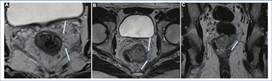

Margen circunferencial de resección

Si bien existen procedimientos mínimamente invasivos para el tratamiento de los estadios T1 y algunos T2, la cirugía de escisión total del mesorrecto (ETM) es en general el tratamiento de elección con vistas a la curación. Dicha cirugía toma como margen de resección a la FMR, con el fin de realizar la escisión completa del recto afectado y el mesorrecto circundante, el cual incluye todas las estructuras vasculares y linfáticas que lo atraviesan3. Por dicha razón, cobra importancia la capacidad de identificar a la FMR que nos otorga la RM de alta resolución, así como también la posibilidad de evaluar su compromiso por parte del tumor11. En la tabla 2 se exponen las circunstancias en las que la FMR se considera comprometida, tomando esos casos como margen circunferencial de resección (MCR) positivo (Fig. 13) y contraindicando por ende al tratamiento quirúrgico, a la vez que por sí mismo es un factor pronóstico de recurrencia local, metástasis a distancia y mal pronóstico8,12,13.